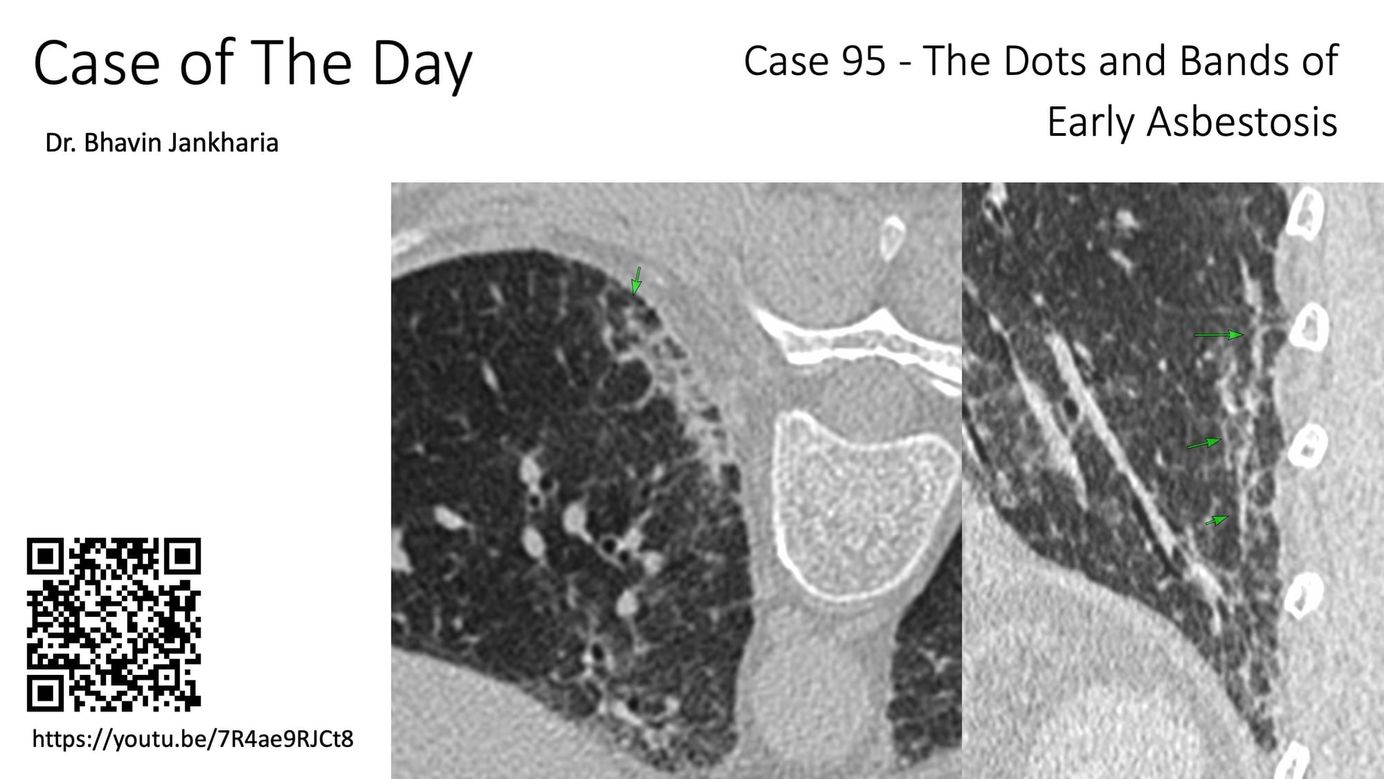

Case of the Day - 095 - 2025 09 03 - The Dots and Bands of Early Asbestosis Paid Members Public

In patients with asbestos exposure, early asbestosis presents in a distinctive manner...however these signs do not help distinguish asbestosis from other ILDs if history of exposure is not known.